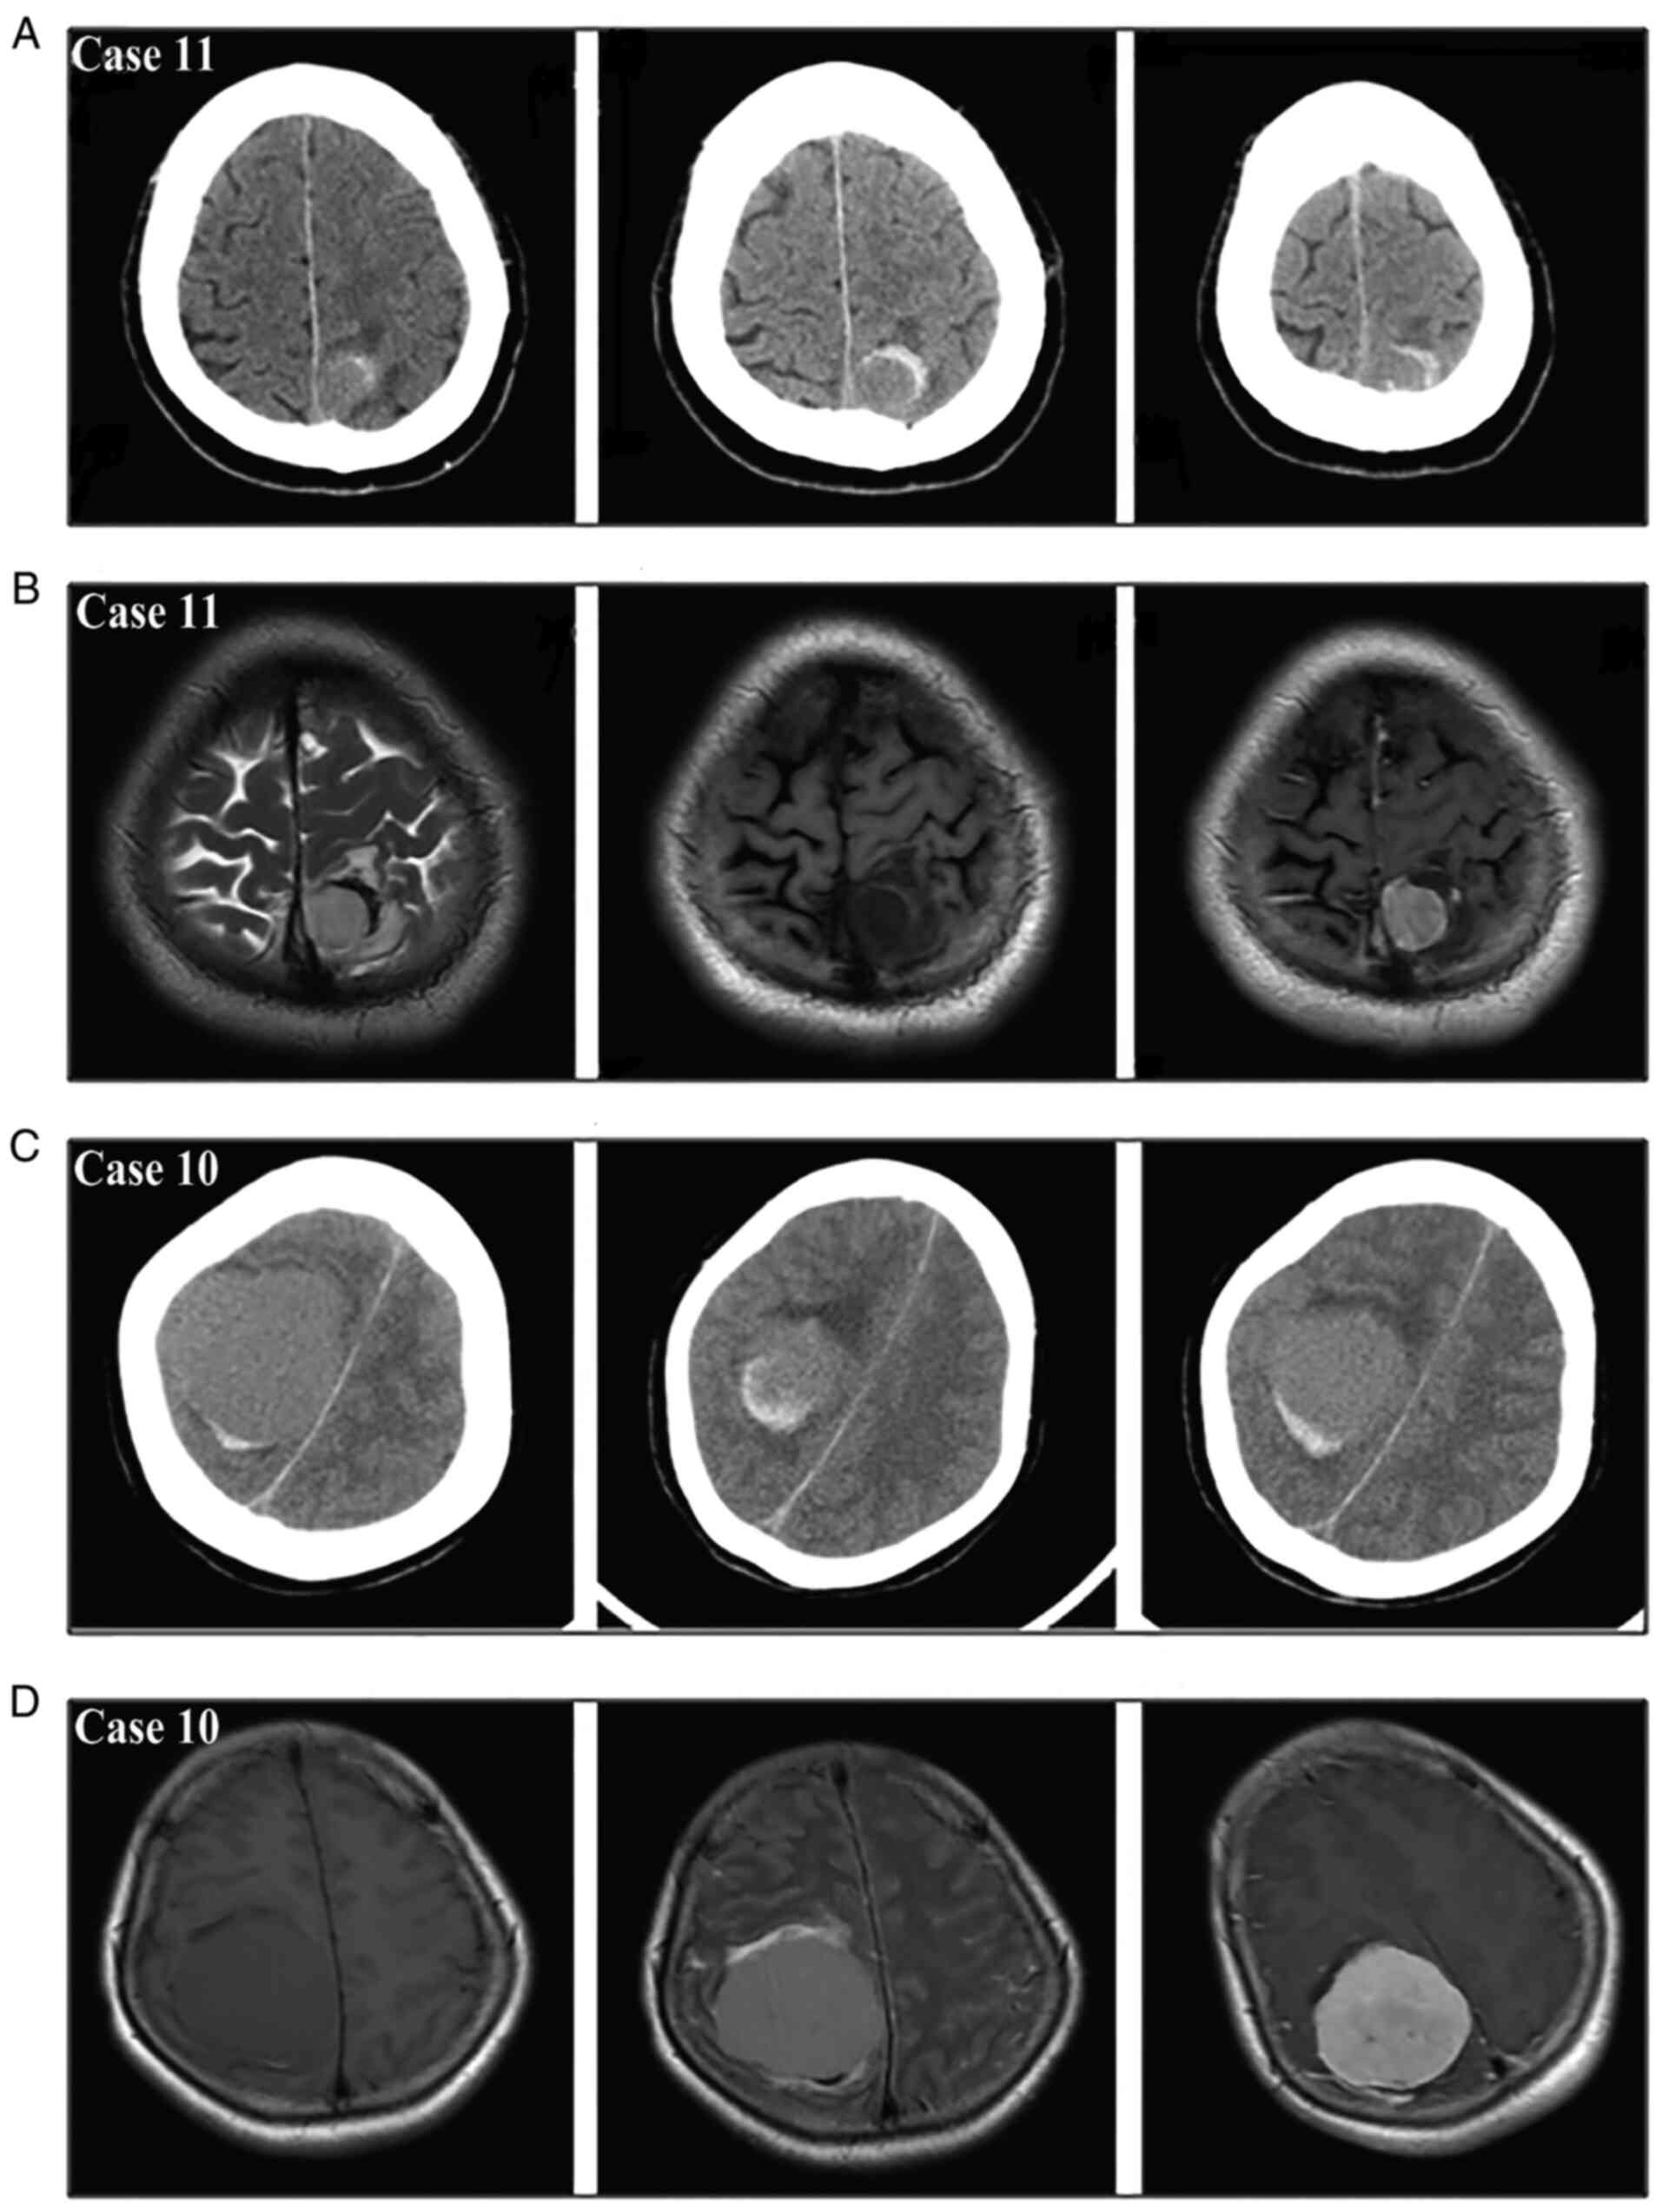

Meningiomas are the most common benign intracranial tumors and frequently present with a gradual onset of neurological deficits; conversely, their acute presentation with hemorrhagic onset appears to be a rare event. Nonetheless, as early surgical evacuation is the foundation of treatment, a timely diagnosis of this rare type of intracranial hemorrhage is necessary. The purpose of the present single‑center study was to investigate the radiological characteristics and propose a new bleeding classification for guiding the diagnosis and treatment. A total of 19 patients consecutively diagnosed with hemorrhagic meningioma were enrolled in this retrospective study. Intracranial extra‑axial mass, tumor‑associated hemorrhage and peritumoral brain edema were the three main radiological features of the hemorrhagic meningiomas. The site of tumor‑associated hemorrhage included the peritumoral space, subarachnoid space, subdural space, brain parenchyma and/or intratumor region. Based on the anatomical relationship between meningioma and hematoma, the spontaneous hemorrhage stemming from meningiomas was further summarized into three bleeding patterns involving purely intratumoral hemorrhage (type I), purely extratumoral hemorrhage (type II) and combined intra/extratumoral hemorrhage (type III); furthermore, the type III hemorrhage usually came from type I bleeding that extended into the surrounding regions. The symptoms in type I patients were generally mild and early surgery was performed following adequate preoperative evaluations. The symptoms in type II patients were mild in certain cases and moderate to severe in others, so early or emergency surgery was chosen according to the clinical status of the patient. Almost all type III patients had moderate to severe symptoms and these patients usually required emergency surgery. In addition, patients with different bleeding types may have different pathological mechanisms underlying the tumor bleeding. Apart from being convenient for diagnosis, this concise and practical bleeding classification may aid in the selection of the treatment strategy and facilitate the understanding of the associated mechanisms.

Figure 1

Figure 2

Figure 3

Figure 4

Figure 5

Figure 6

Figure 7

Figure 8

Figure 9